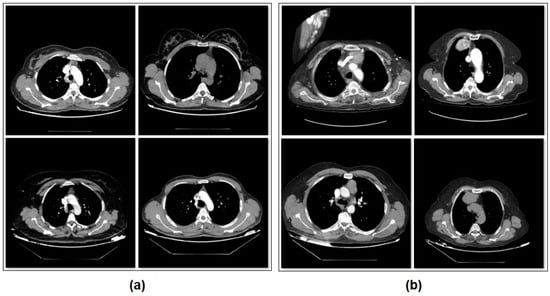

The dataset consists of two classes. The number of images with thymoma disease is 384. The number of images without thymoma is 384. The images in the dataset are equally classified and consist of a total of 768 images. A sample subset of images belonging to the types of the dataset is shown in Figure 1.

Figure 1. Sample images from the dataset categories: (a) patients without thymoma, and (b) patients with thymoma.